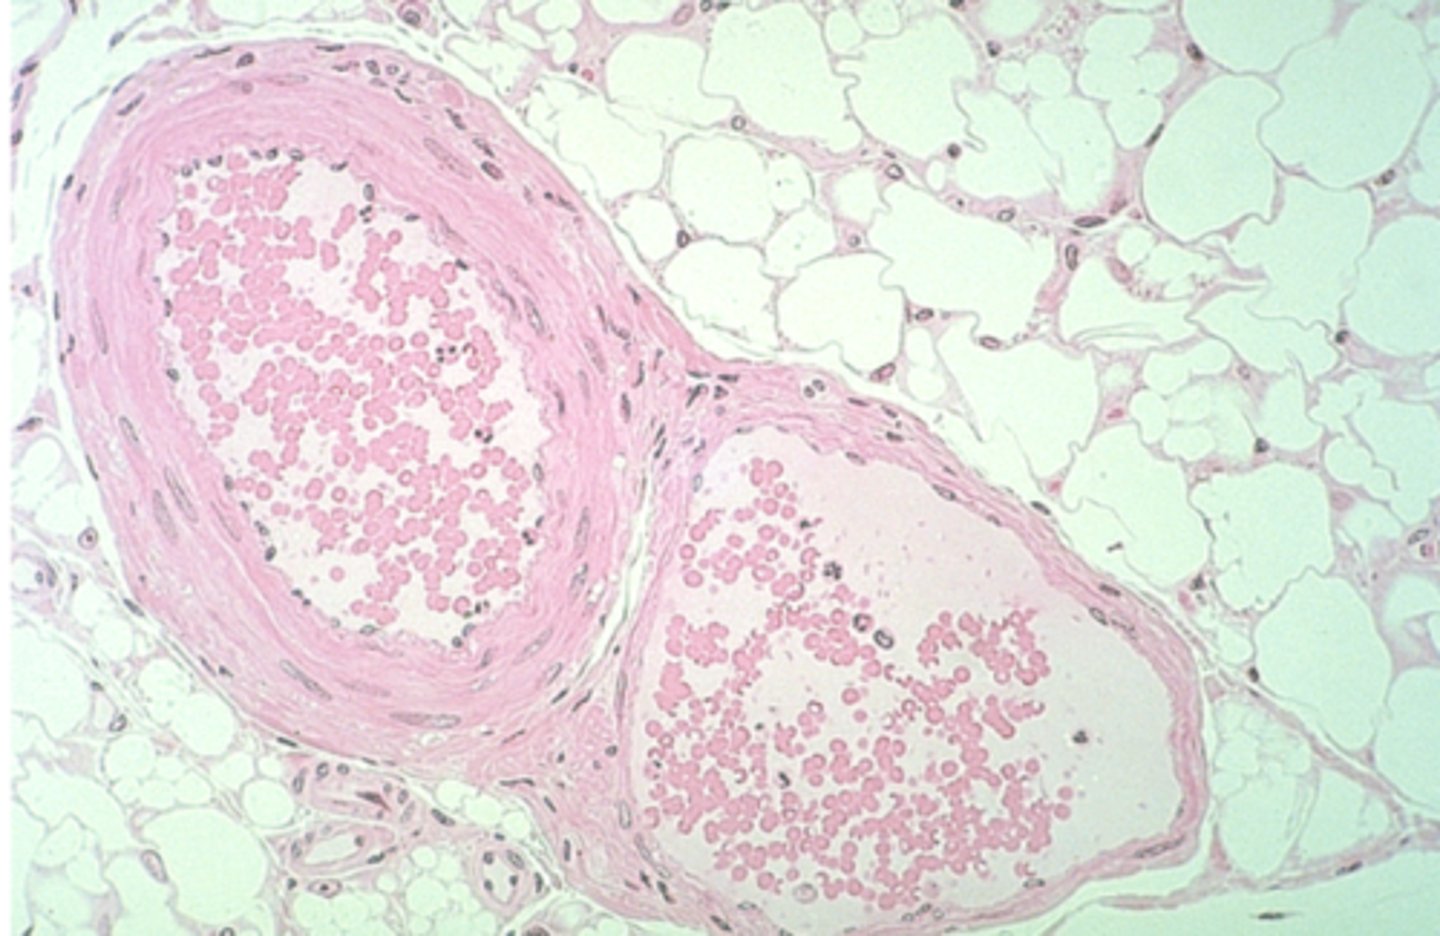

artery

what is this?

vein

what is this?

thicker inner wall

How to identify an artery

thinner inner wall

How to identify a vein